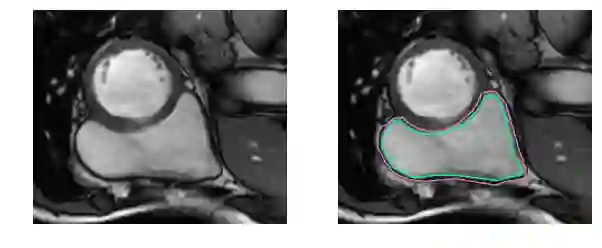

撇开医学术语不谈,要识别RV就更困难了。左心室是一个厚壁圆环,而右心室是一个形状不规则的物体,有薄的壁,有时会与周围的组织混合在一起。这是MRI快照右心室内壁和外壁(心内膜和心外膜)的手工绘制轮廓:

这是一个分割起来很容易的例子。这一个比较困难: